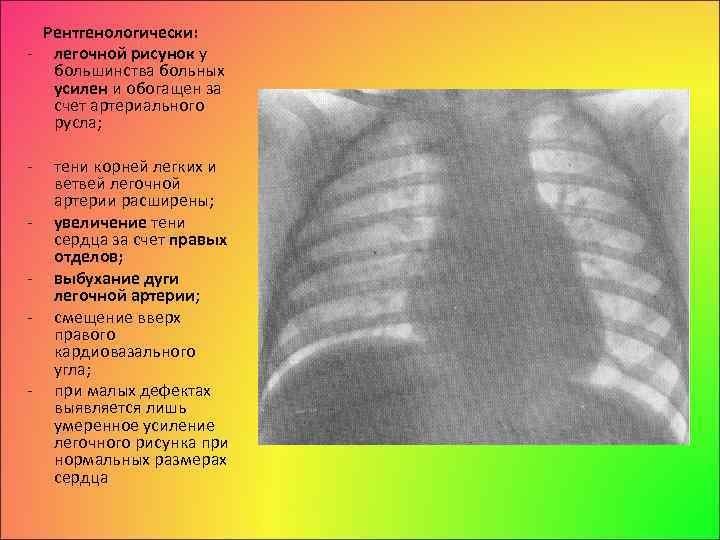

Усиление сосудистого рисунка легких на рентгене - это явление, которое может быть наблюдаемо при проведении рентгенологического исследования органов дыхания. В результате усиления сосудистого рисунка, на снимке становятся более заметными сосуды, расположенные внутри легких. Это может свидетельствовать о различных патологических процессах, таких как воспаление легких, обструкция дыхательных путей или сердечная недостаточность. Усиление сосудистого рисунка является важным признаком для постановки диагноза и выбора оптимального лечения. Однако, для точной интерпретации рентгеновского снимка необходимо учитывать и другие клинические данные, а также провести дополнительные исследования, если необходимо.